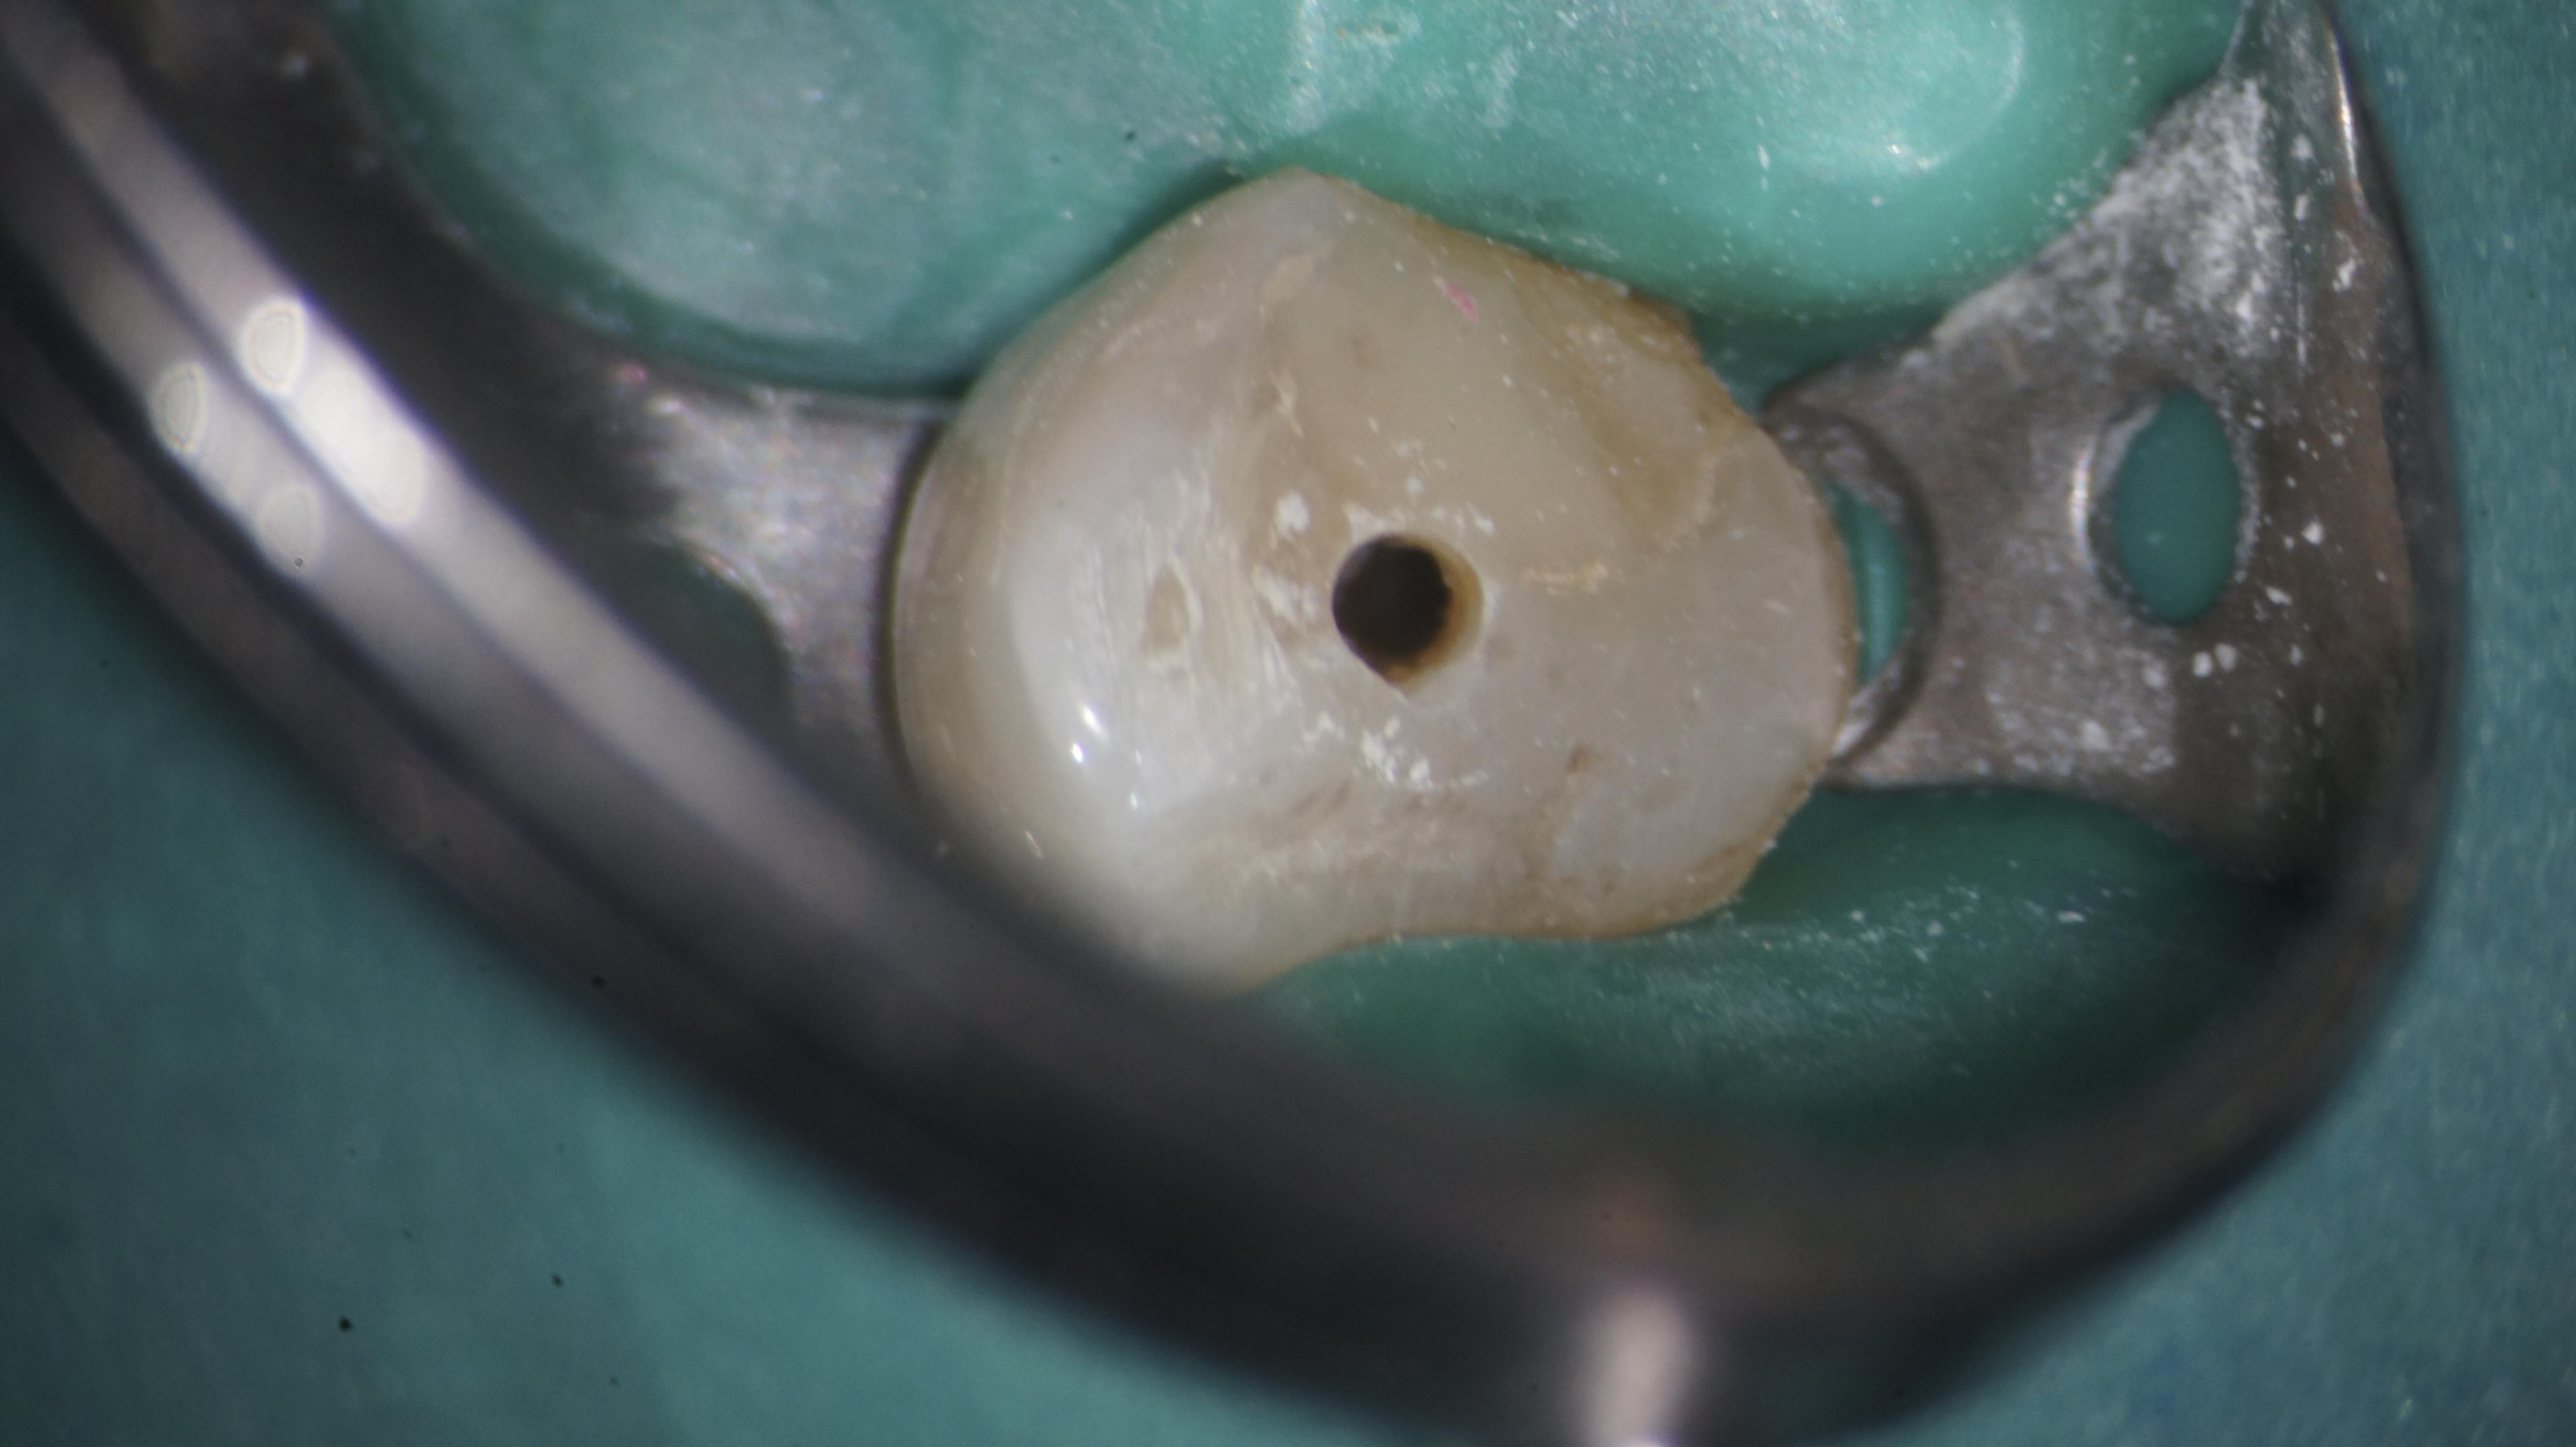

UK-3 Veröffentlicht 12. Februar 2014 am 4912 × 2760 in Neue Wege gehen Zustand nach initialer Trepanation